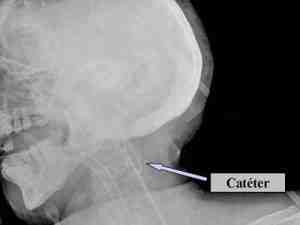

Bucle del catéter del golfo de la yugular

Resumen

Los meningiomas son tumores benignos de

crecimiento lento, que representan el 15-20% de los tumores

intracraneales. El 90% de los meningiomas son intracraneales. Es más

común en mujeres en la sexta década de la vida.

La cirugía es el tratamiento de elección

para la mayoría de los pacientes con meningiomas. La monitorización de

la saturación venosa de oxígeno del golfo de la yugular (SjO2) forma

parte de la monitorización multimodal en el paciente neurológico.